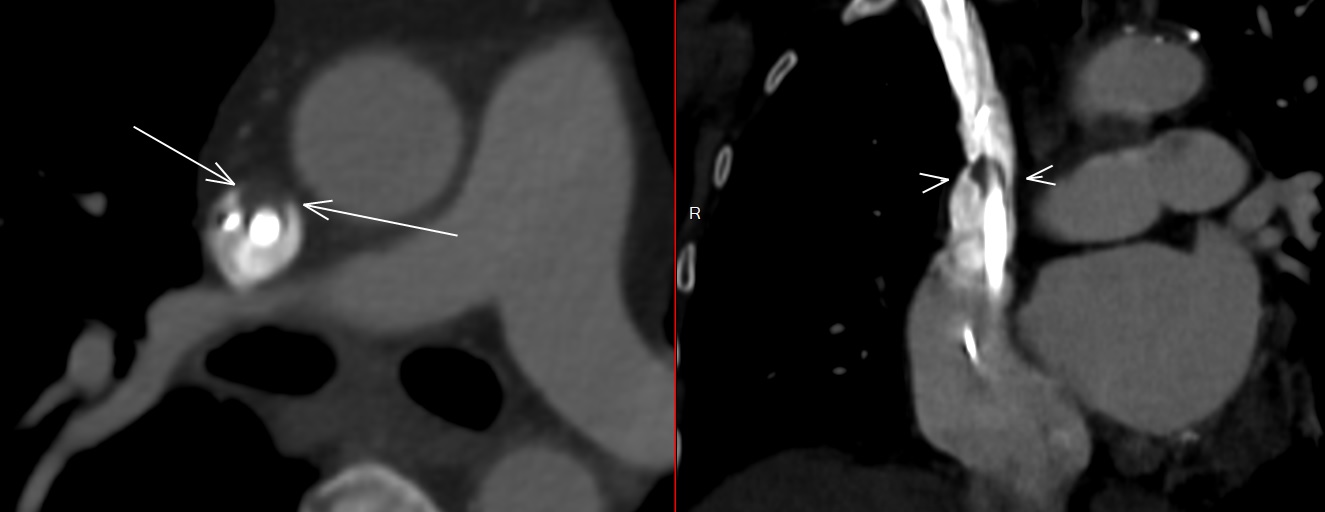

Artère Carotide